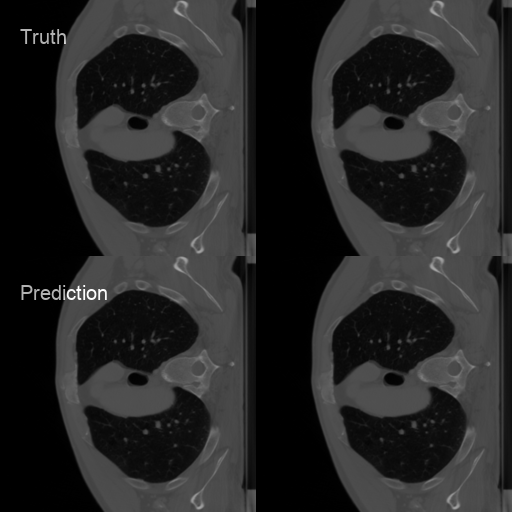

I developed a deep-learning-based approach based on U-Net as a noninvasive technique to provide information about bony changes and disease changing in CT images for temporomandibular joint osteoarthritis.